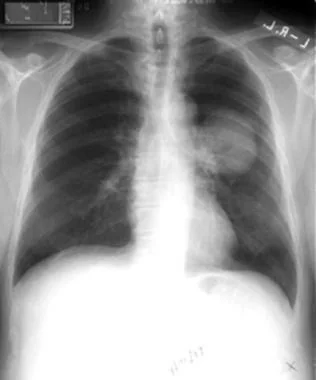

肺空洞:

cavity_lung_abscess_2.jpg?mtime=20210304211317&focal=none

肺實質

0a1f5edc85aa58d5780928cb39b08659c1fc4d6d7c7dce2f8db1d63c7c737234_gallery.jpeg